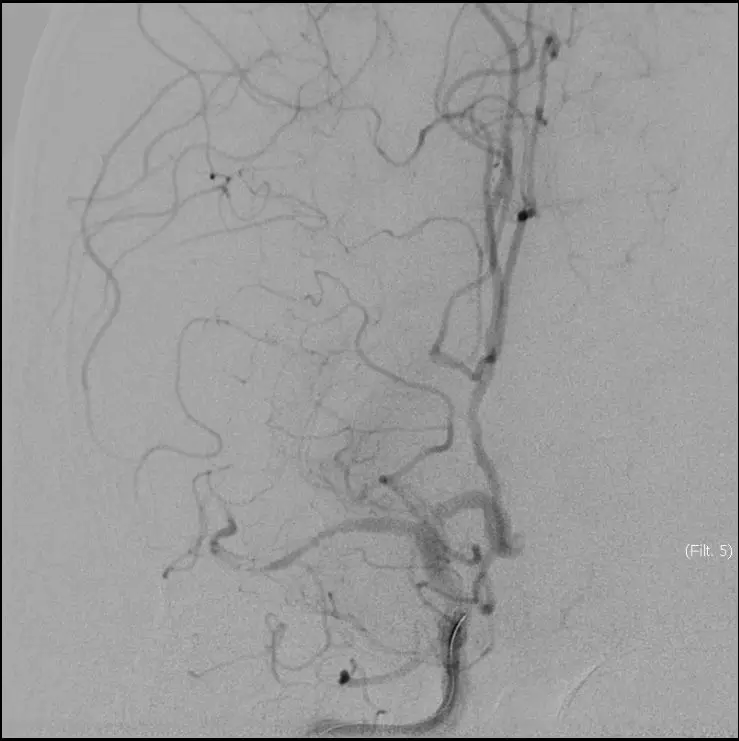

立即DSA(08-03日 13:24分)

5MIN后

5MIN后

赛诺 2.0*15mm球囊扩张

5MIN后

赛诺 2.0*15mm球囊扩张

5MIN后

10MIN后

再次与家属沟通病情,交代支架植入风险,家属表示理解,准备支架解脱

5MIN后

再次观察10MIN后

16:30分

手术结束